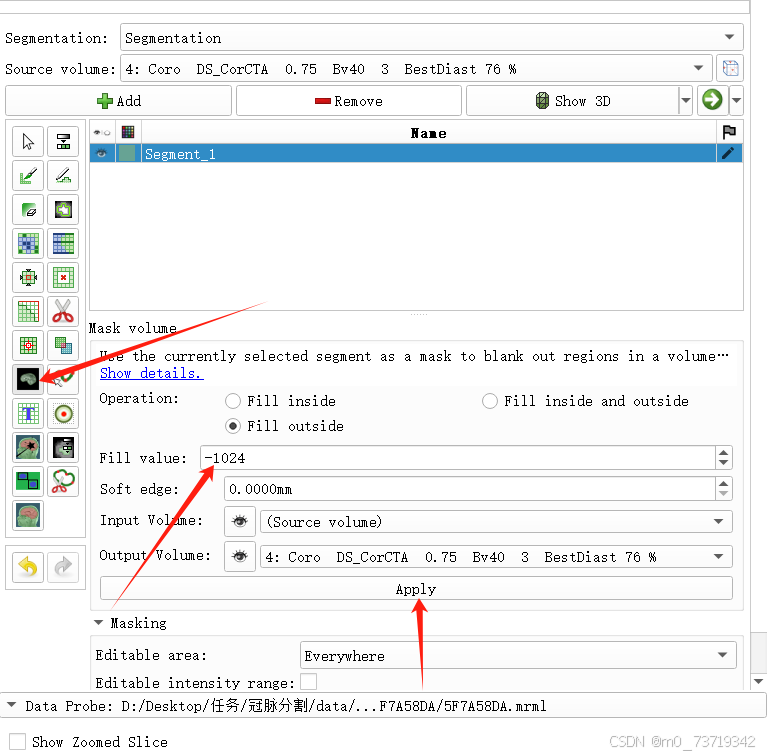

然后依次点击下图所示按钮

可见三维图像中分割完毕